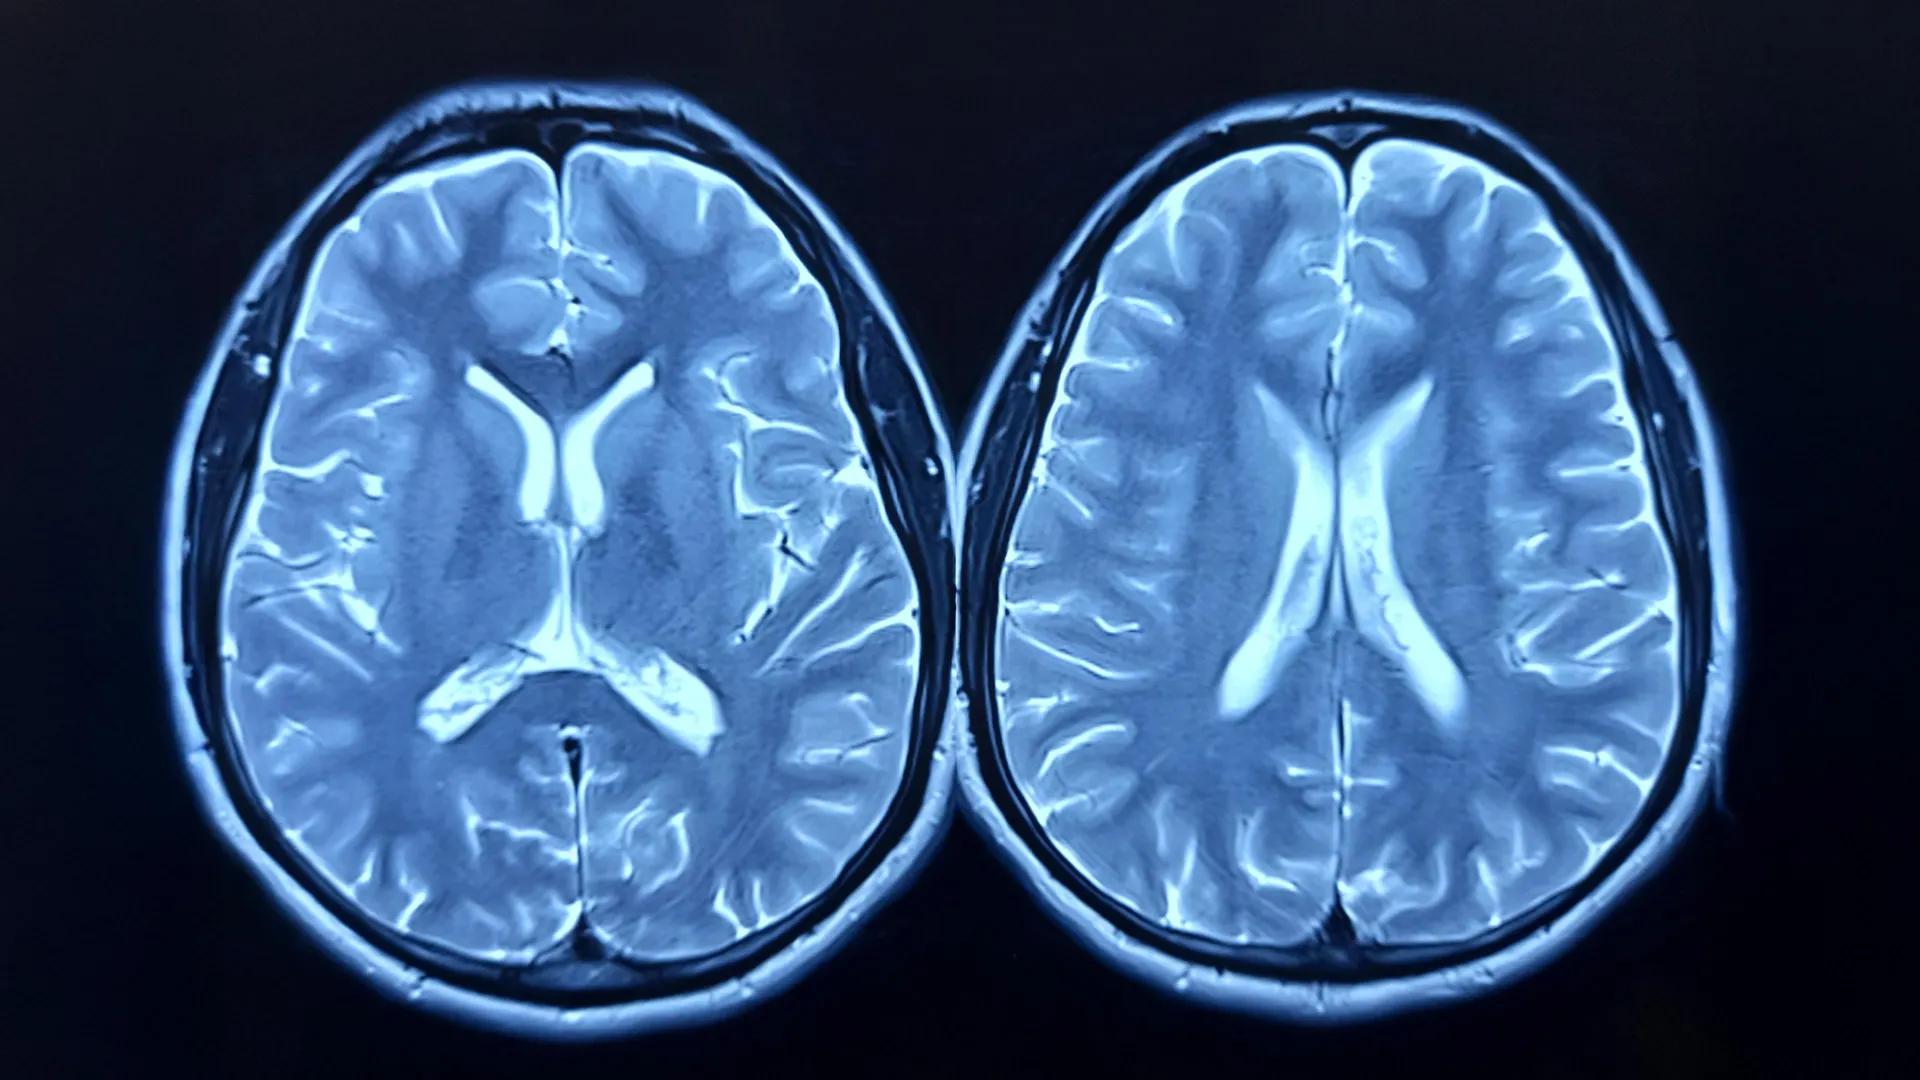

Scientists Find Intelligence May Come From The Brain Working As One System

For decades, scientists have studied the brain like a collection of separate tools. One system handles memory. Another manages attention. Others process language, perception or reasoning. Each network has been mapped and studied individually, leading to major discoveries about how the brain works. But one big question has remained. How do all those separate systems combine to produce a single, unified mind? Researchers at the University of Notre Dame believe they are getting closer to an answer. In a new study published in Nature Communications, scientists found evidence that human intelligence may come not from one specific brain region, but from how the entire brain works together. “Neuroscience has been very successful at explaining what particular networks do, but much less successful at explaining how a single, coherent mind emerges from their interaction,” said Aron Barbey, professor of psychology at Notre Dame. The research focuses on something psychologists have noticed for more than a century. People who perform well in one cognitive skill, such as memory or attention, often perform well in others. This pattern is known as general intelligence. It influences how people learn, solve problems and adapt to challenges throughout life. Scientists have long known the pattern exists, but they have struggled to explain why. “The problem of intelligence is not one of functional localization,” Barbey said. Many studies have tried to pinpoint intelligence to specific regions in the brain, especially areas in the frontal and parietal cortex. But Barbey says the more important question may be how the brain’s networks communicate and coordinate with each other. To explore that idea, researchers tested what they call the Network Neuroscience Theory. Instead of viewing intelligence as a single skill or brain region, the theory suggests intelligence emerges from the overall organization of the brain’s networks and how efficiently they share information. The research team analyzed brain imaging and cognitive performance data from 831 adults in the Human Connectome Project. They then tested their findings against a second group of 145 adults in the INSIGHT Study. By combining data on both brain structure and brain activity, scientists created a detailed map of how large-scale brain networks interact. The results supported a different way of thinking about intelligence. Rather than existing in one place, intelligence appears to arise from cooperation among many brain systems. “We found evidence for system-wide coordination in the brain that is both robust and adaptable,” said Ramsey Wilcox, the study’s lead author. “This coordination does not carry out cognition itself, but determines the range of cognitive operations the system can support.” The researchers identified several key features that appear to shape intelligence. First, many brain networks must work together. Tasks are distributed across specialized systems, which then combine their information. Second, communication between distant parts of the brain is essential. Long-range connections act like shortcuts, linking far-apart regions and allowing them to exchange information quickly. Third, certain regulatory regions act as coordinators, directing which networks activate when solving problems or making decisions. Finally, intelligence depends on balance. Local groups of neurons need to work efficiently while still staying connected to the wider brain network. When those elements work together smoothly, thinking becomes more flexible and effective. Across both groups in the study, differences in intelligence were closely tied to these large-scale organizational patterns rather than to any single brain area. “General intelligence becomes visible when cognition is coordinated,” Barbey said, “when many processes must work together under system-level constraints.” The findings could help explain several patterns seen throughout human life. For example, intelligence often increases during childhood as brain networks become more connected. It may decline with aging as those connections weaken. And widespread brain injuries can disrupt intelligence even when individual regions remain intact. The research could also influence the future of artificial intelligence. Today’s AI systems are extremely good at specific tasks, such as recognizing images or generating text. But they often struggle to apply knowledge across different situations. Barbey says the human brain offers a clue as to why. “Many AI systems can perform specific tasks very well, but they still struggle to apply what they know across different situations,” he said. “Human intelligence is defined by this flexibility — and it reflects the unique organization of the human brain.” The study suggests that building truly adaptable artificial intelligence may require designing systems that mirror the brain’s network-wide coordination, rather than simply expanding specialized tools. In other words, the secret to intelligence may not lie in any single part of the brain. It may lie in how the whole system works together.